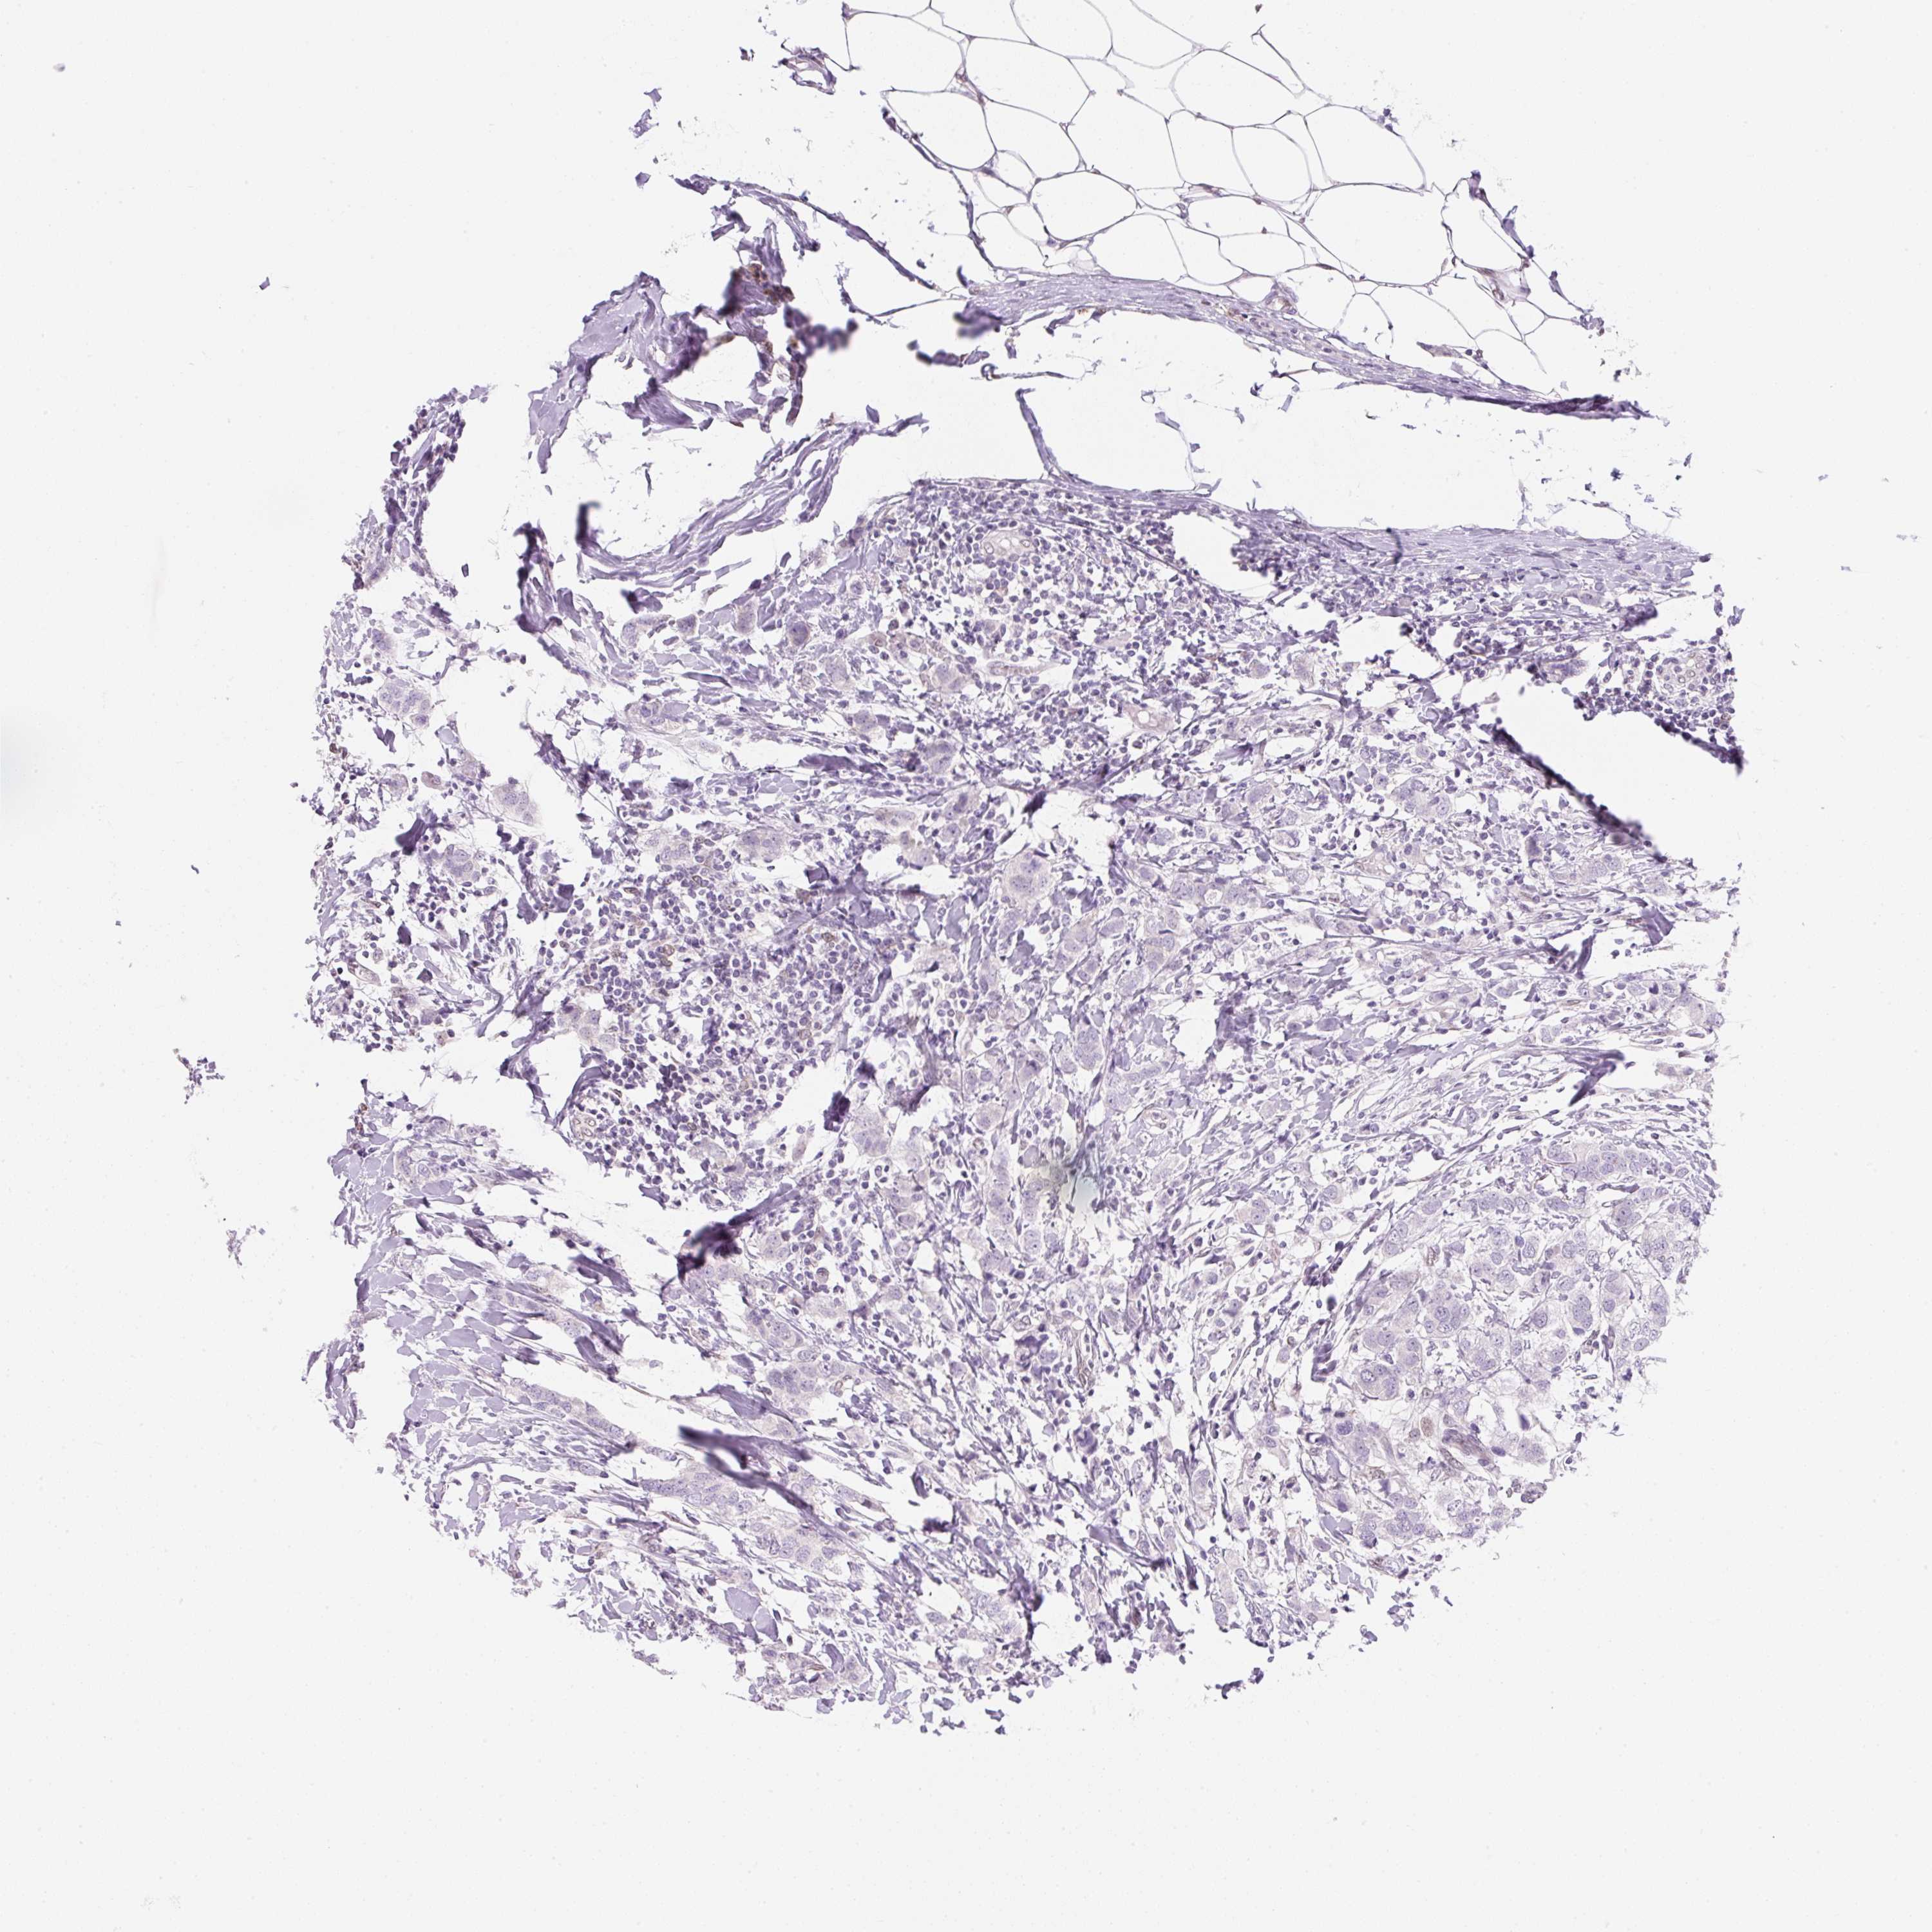

CANCER BREAST CANCER Show tissue menu

BRCA TCGA BRCA VALIDATION PROTEIN EXPRESSION